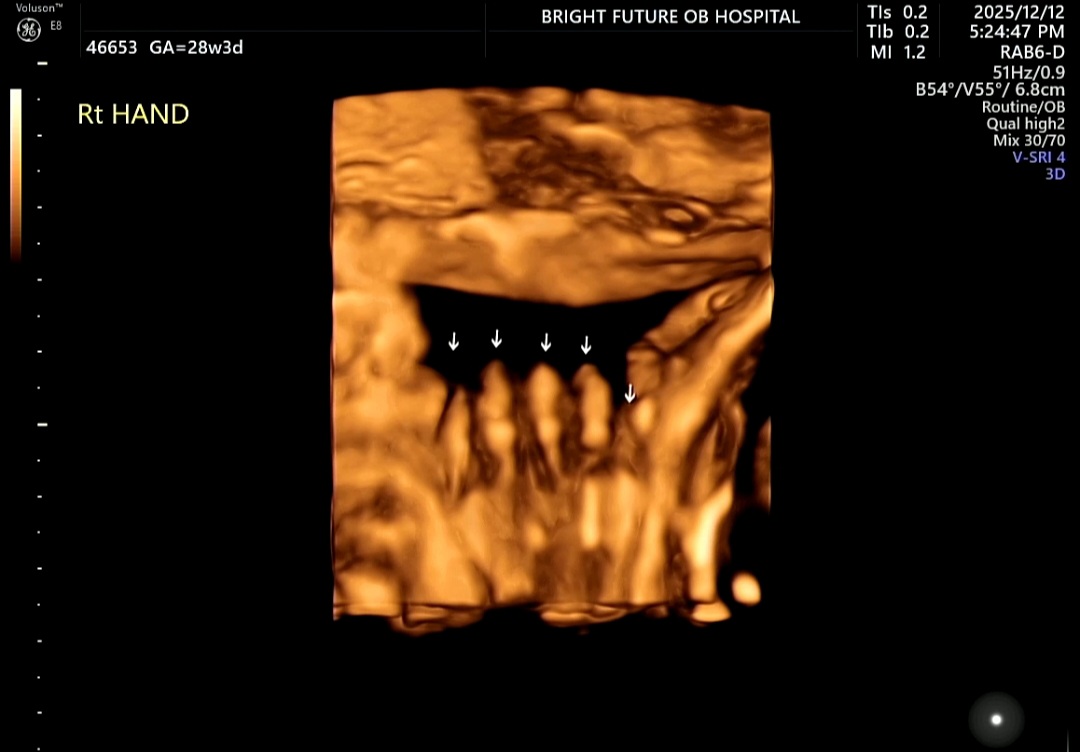

손·발, 심장, 장기까지 하나하나 확인

얼굴 확인 후에는 양손과 양발도 차례대로 관찰했다.

인형처럼 작은 발, 또렷한 발가락 다섯 개.

영상에 집중해 손가락과 발가락 개수를 확인하고 나니 마음이 놓였다.